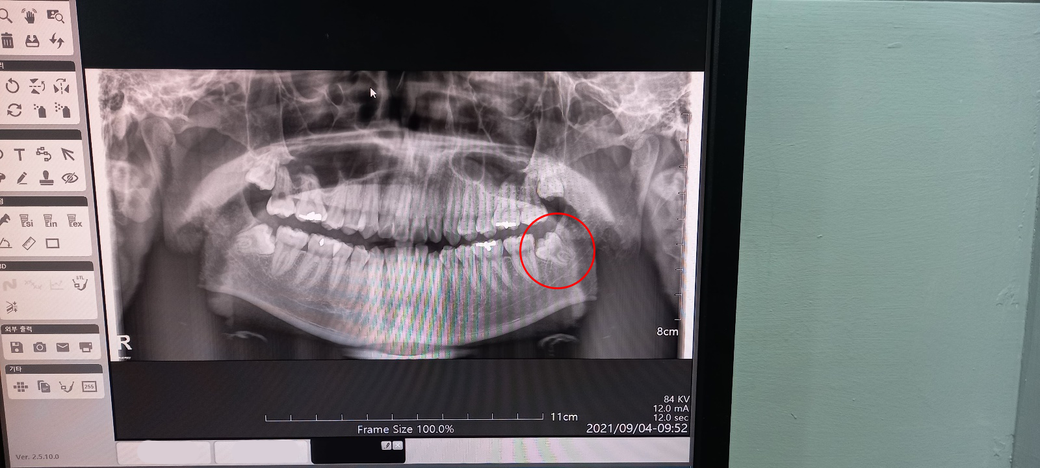

입대 약 5일 남은 군인인데 매복 사랑니가 살짝 아픕니다. 얼마 남지 않았지만 뽑아야할까요?

8월 22일 입대를 앞두고 갑작스레 왼쪽 아래 사랑니가 아픕니다.

바로 평소에 가던 치과에 가서 CT 찍어본 결과 썩지는 않아 일단 소독하고 소염제와 진통제 등 처방받아 돌아왔습니다.

신경이랑 가까이 위치해서 조심해야한다고도 말씀하셨구요.

• 1번 째 사진